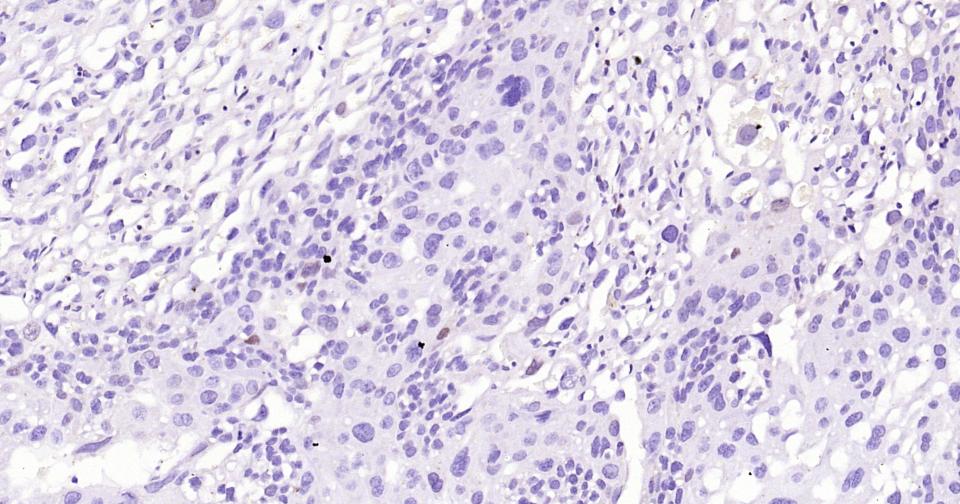

Paraformaldehyde-fixed, paraffin embedded Human Lung Cancer; Antigen retrieval by boiling in sodium citrate buffer (pH6.0) for 15 min; Antibody incubation with SOX9 Monoclonal Antibody, Unconjugated(bsm-63031R) at 1:400 overnight at 4°C, followed by conjugation to the bs-0295G-HRP and DAB (C-0010) staining.